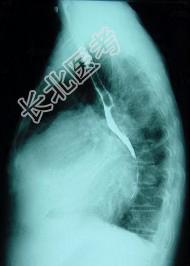

- 单项选择题对如下心脏左侧位片描述正确的是 ( )

A、右心房增大

B、左心房Ⅰ度增大

C、左心房Ⅲ度增大

D、正常心脏

E、以上均错